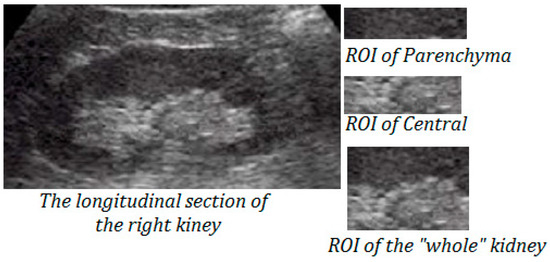

3. Application for Characterization of Kidney Ultrasound Images

- As a region of interest, the parenchyma remains more representative than the central region. Indeed, for the parenchyma ROI, the best classification accuracy rate, which reaches about 76%, is obtained using the combined method with seven features, while the test classification, using the subset of seven features, is 73.3%.

- The central region remains the least representative with the best classification accuracy obtained using the combined method. Indeed, the classification accuracy rate reached about 62.6%, and test classification is about 60%.